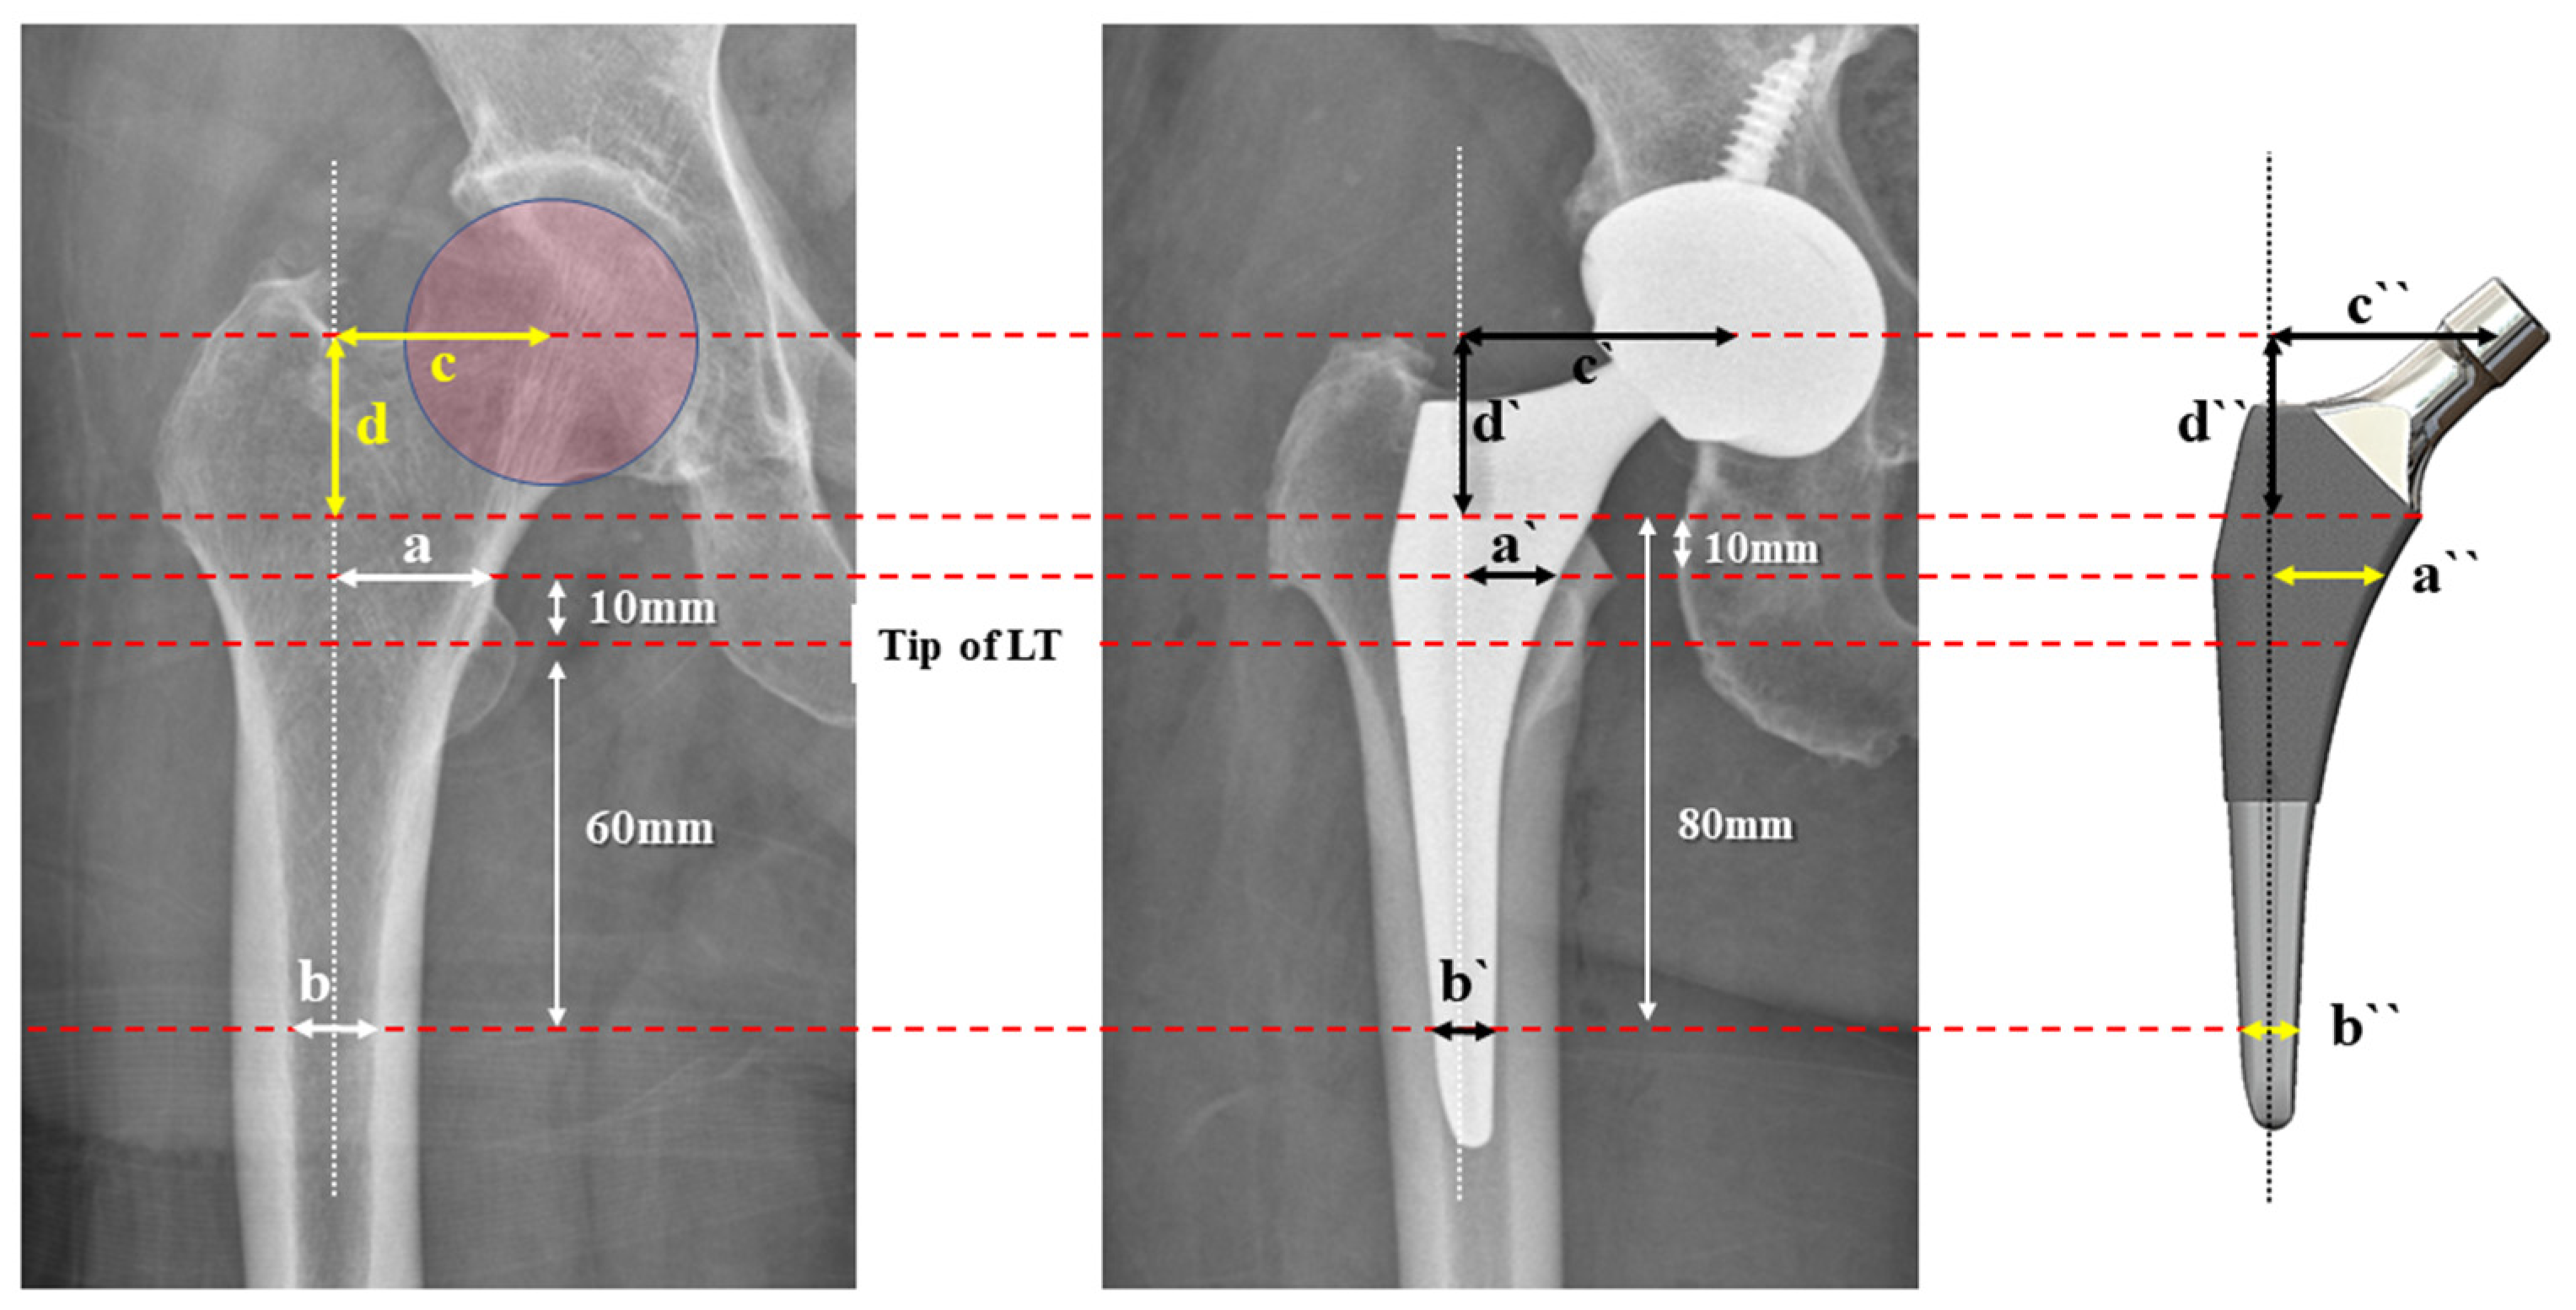

2.3. Radiographic Measurements

2.5. ML Width Analysis

2.6. Offset Analysis